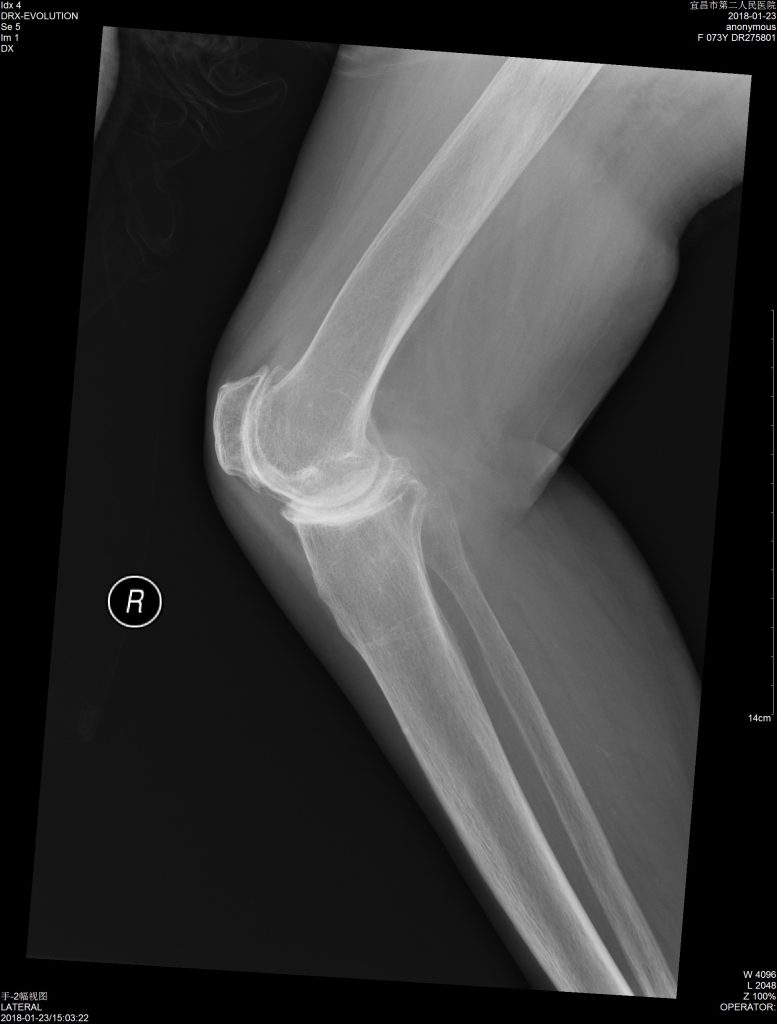

医学影像-诊断

X IMAGE DISPLAY-Provide an intuitive Feel